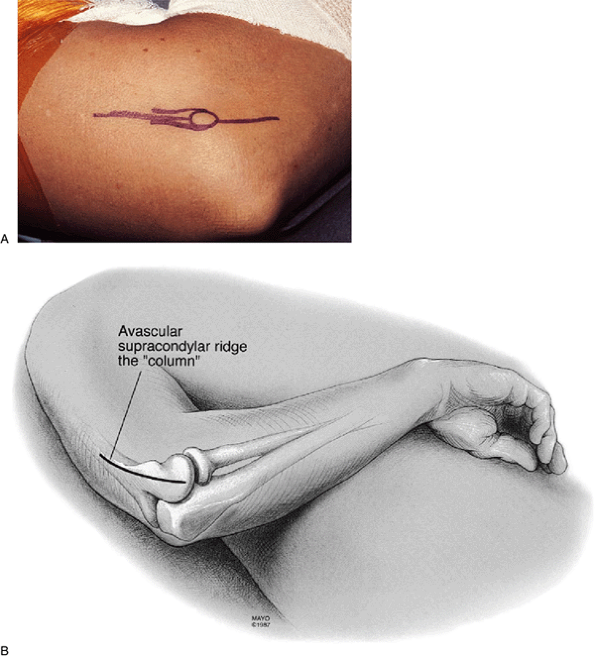

Figure 21-1. A:

The concept of the column procedure. Identify the supracondylar ridge and approach the anterior and posterior aspects of the capsule as necessary. Osteophytes are readily removed from the coronoid process or the olecranon. B: Relevant anatomy of the “column.” The anterior and posterior aspects of the lateral column are identified (solid lines). (Abbreviations: ECRL, extensor carpi radialis longus; ECRB, extensor carpi radialis brevis.) |

column procedure consists of arthrotomy, release of the anterior and

posterior capsule if needed, and excision of osteophytes through a

limited lateral approach (Fig. 21-1).